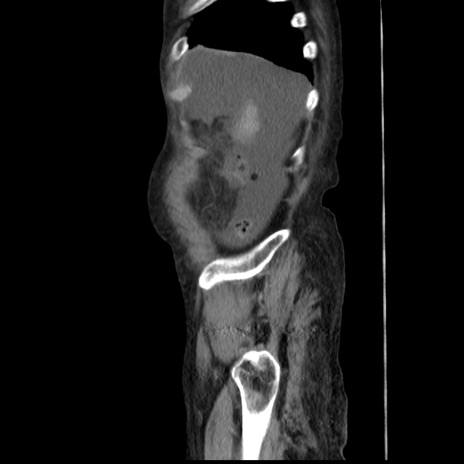

症例31(矢状断像)

【症例】80歳代 女性

【主訴】腹部膨満感

【現病歴】他院にて肝硬変にてフォロー中。1週間前から便秘、腹部膨満感、臍部腫瘤あり受診となる。

【既往歴】肝硬変

【身体所見】腹部膨隆あり、皮膚変化なし、疼痛なし。

【データ】WBC 4600、CRP 0.25